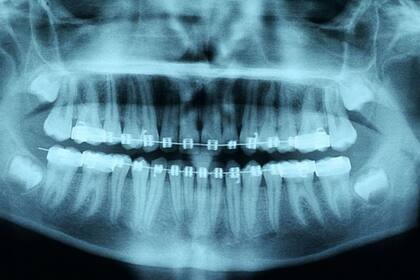

Algunos de los factores que tienen en cuenta los dentistas para recomendar su uso es la salud de los tejidos duros y blandos de la boca, los dientes y las encías, así como si las raíces de los dientes pueden sostener un movimiento. Por eso es que las radiografías son fundamentales en este proceso.

Las raíces de los dientes del paciente eran demasiado cortas para soportar la presión de los alineadores, lo que se habría detectado en una radiografía.

Según las asociaciones dentales británicas, los escáneres 3D y los moldes de dientes que se hace uno mismo utilizados en ortodoncia a distancia no son suficientes para recomendar el uso de alineadores.